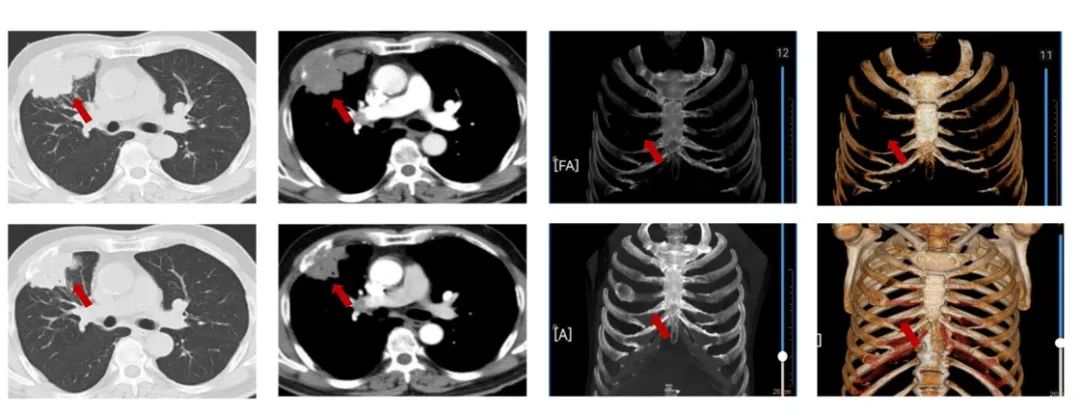

患者王XX,男,54岁,2023年4月以“咳嗽1个月”入院,PS1分,高血压3年,行替米沙坦40毫克日1次口服血压控制好,否认冠心病,糖尿病等病史,吸烟史:吸烟30年,每天20支。肺CT(外院,2023-3):右肺中叶肿物,32mm*37mm,边缘见分叶,纵隔淋巴结肿大,右肺中叶中心型肺癌?邻近上叶前段局部受累不除外。右肺中叶炎症。双肺气肿、肺大泡。肝脏多发小囊肿。支气管镜:右肺中叶见新生物,表面有坏死物附着,堵塞管腔,取病理。病理:鳞癌。PD-L1(DAKO 22C3)(+,CPS=20)。cT2bN2M0,ⅢA期。经MDT讨论后,患者为可切除手术患者,建议新辅助治疗。给予患者3周期特瑞普利单抗+紫杉醇/卡铂治疗,3周期评效PR。

图3:由上至下分别展示基线(A.)及免疫化学治疗后改变(B.)。红色箭头指示病灶位置,由左至右分别为右肺肿物肺窗、右肺肿物纵隔窗。